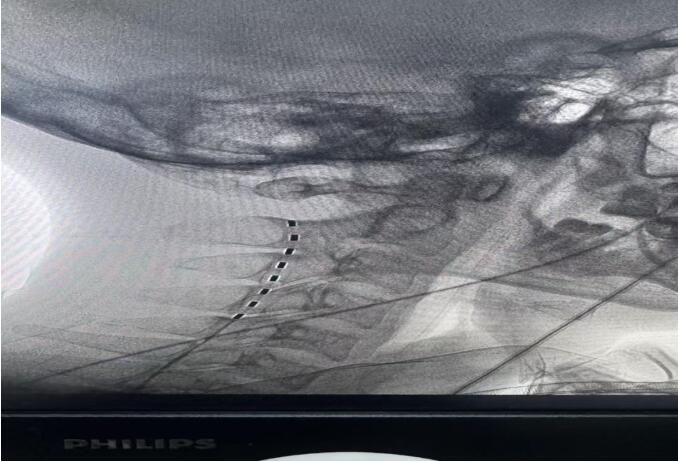

手术中,团队凭借丰富的功能神经外科经验,通过微创方式将短程刺激电极精准植入患者颈段脊髓的硬脊膜外。电脉冲由此发出,温和而持续地刺激上行性网状激活系统——这是维持大脑觉醒与意识的关键通路。整个手术历时约30分钟,过程平稳,患者生命体征始终稳定。